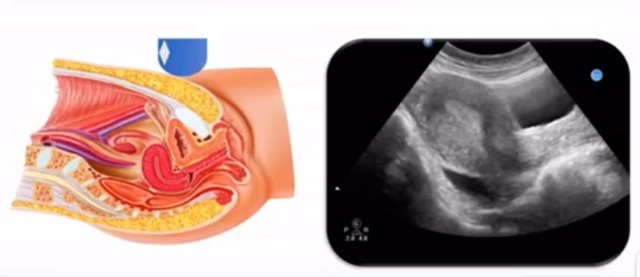

女性生殖系統(tǒng)包括內(nèi)、外生殖器官及其相關(guān)組織以及鄰近器官,其中內(nèi)生殖器是我們超聲檢查的主要對象。那么內(nèi)生殖器包括陰道、子宮還有輸卵管及卵巢。輸卵管及卵巢稱為子宮附件。子宮是倒置梨形,但是它是空腔厚壁肌性器官。它的正常值在育齡婦女。超聲探頭放在貼近腹壁盆腔上面位置,來看這個子宮在超聲上面的表現(xiàn)。從輪廓上來講,和示意圖是一樣的。這就是在超聲上面顯示的一個子宮的圖片。子宮在不同的時期與子宮頸的比例。成年婦女指的是育齡婦女為2:1子宮體是比較大的,嬰兒期為1:2說明宮頸比較大,絕經(jīng)期1:1。所以我們在看到子宮圖時候可以根據(jù)宮體宮頸比例大致可以推測屬于哪個時期的婦女。另外還可以根據(jù)比例大小來推斷是一個正常子宮還是異常子宮。

子宮從外到內(nèi),漿膜層、肌層、粘膜層。宮體部宮頸為梭形結(jié)構(gòu)。宮腔為上寬下窄的三角形,連接為峽部。子宮有什么功能呢?月經(jīng)血產(chǎn)生跟排出通道,精子運行通道受精作用。囊胚著床及胎兒發(fā)育、生長的場所。分娩時產(chǎn)生宮縮使胎兒、胎盤娩出。未孕的子宮是很小的,已孕子宮就非常大,平均胎兒都有6斤重。所以這個后壁就體現(xiàn)出來。輸卵管由子宮角部向外延伸,為一對細(xì)長而彎曲的管道,呈管狀中空結(jié)構(gòu),大概長度是8-14厘米,粗1-4毫米,它的下方為卵巢和闊韌帶。間質(zhì)部是厚一點的,峽部是比較窄的地方,壺腹部,漏斗部。正常情況下,輸卵管在普通超聲DR難以顯示。